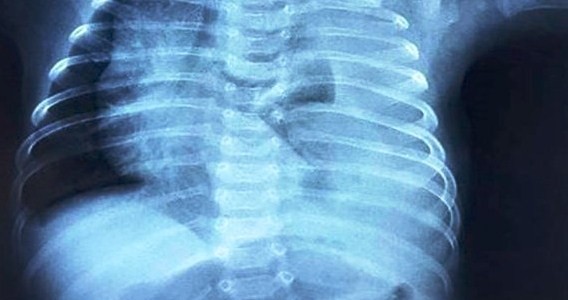

Em bé nguy kịch vì nửa lít dịch tràn vào màng phổi mỗi ngày

Mẹ và bé -  15/12/2019

Bệnh viện Nhi đồng 2 TP.HCM cho biết, bệnh nhi nhập trong tình trạng khó thở nặng. Kết quả chụp X-quang phổi cho thấy một lỗ rò dấn đến tràn dịch màng...